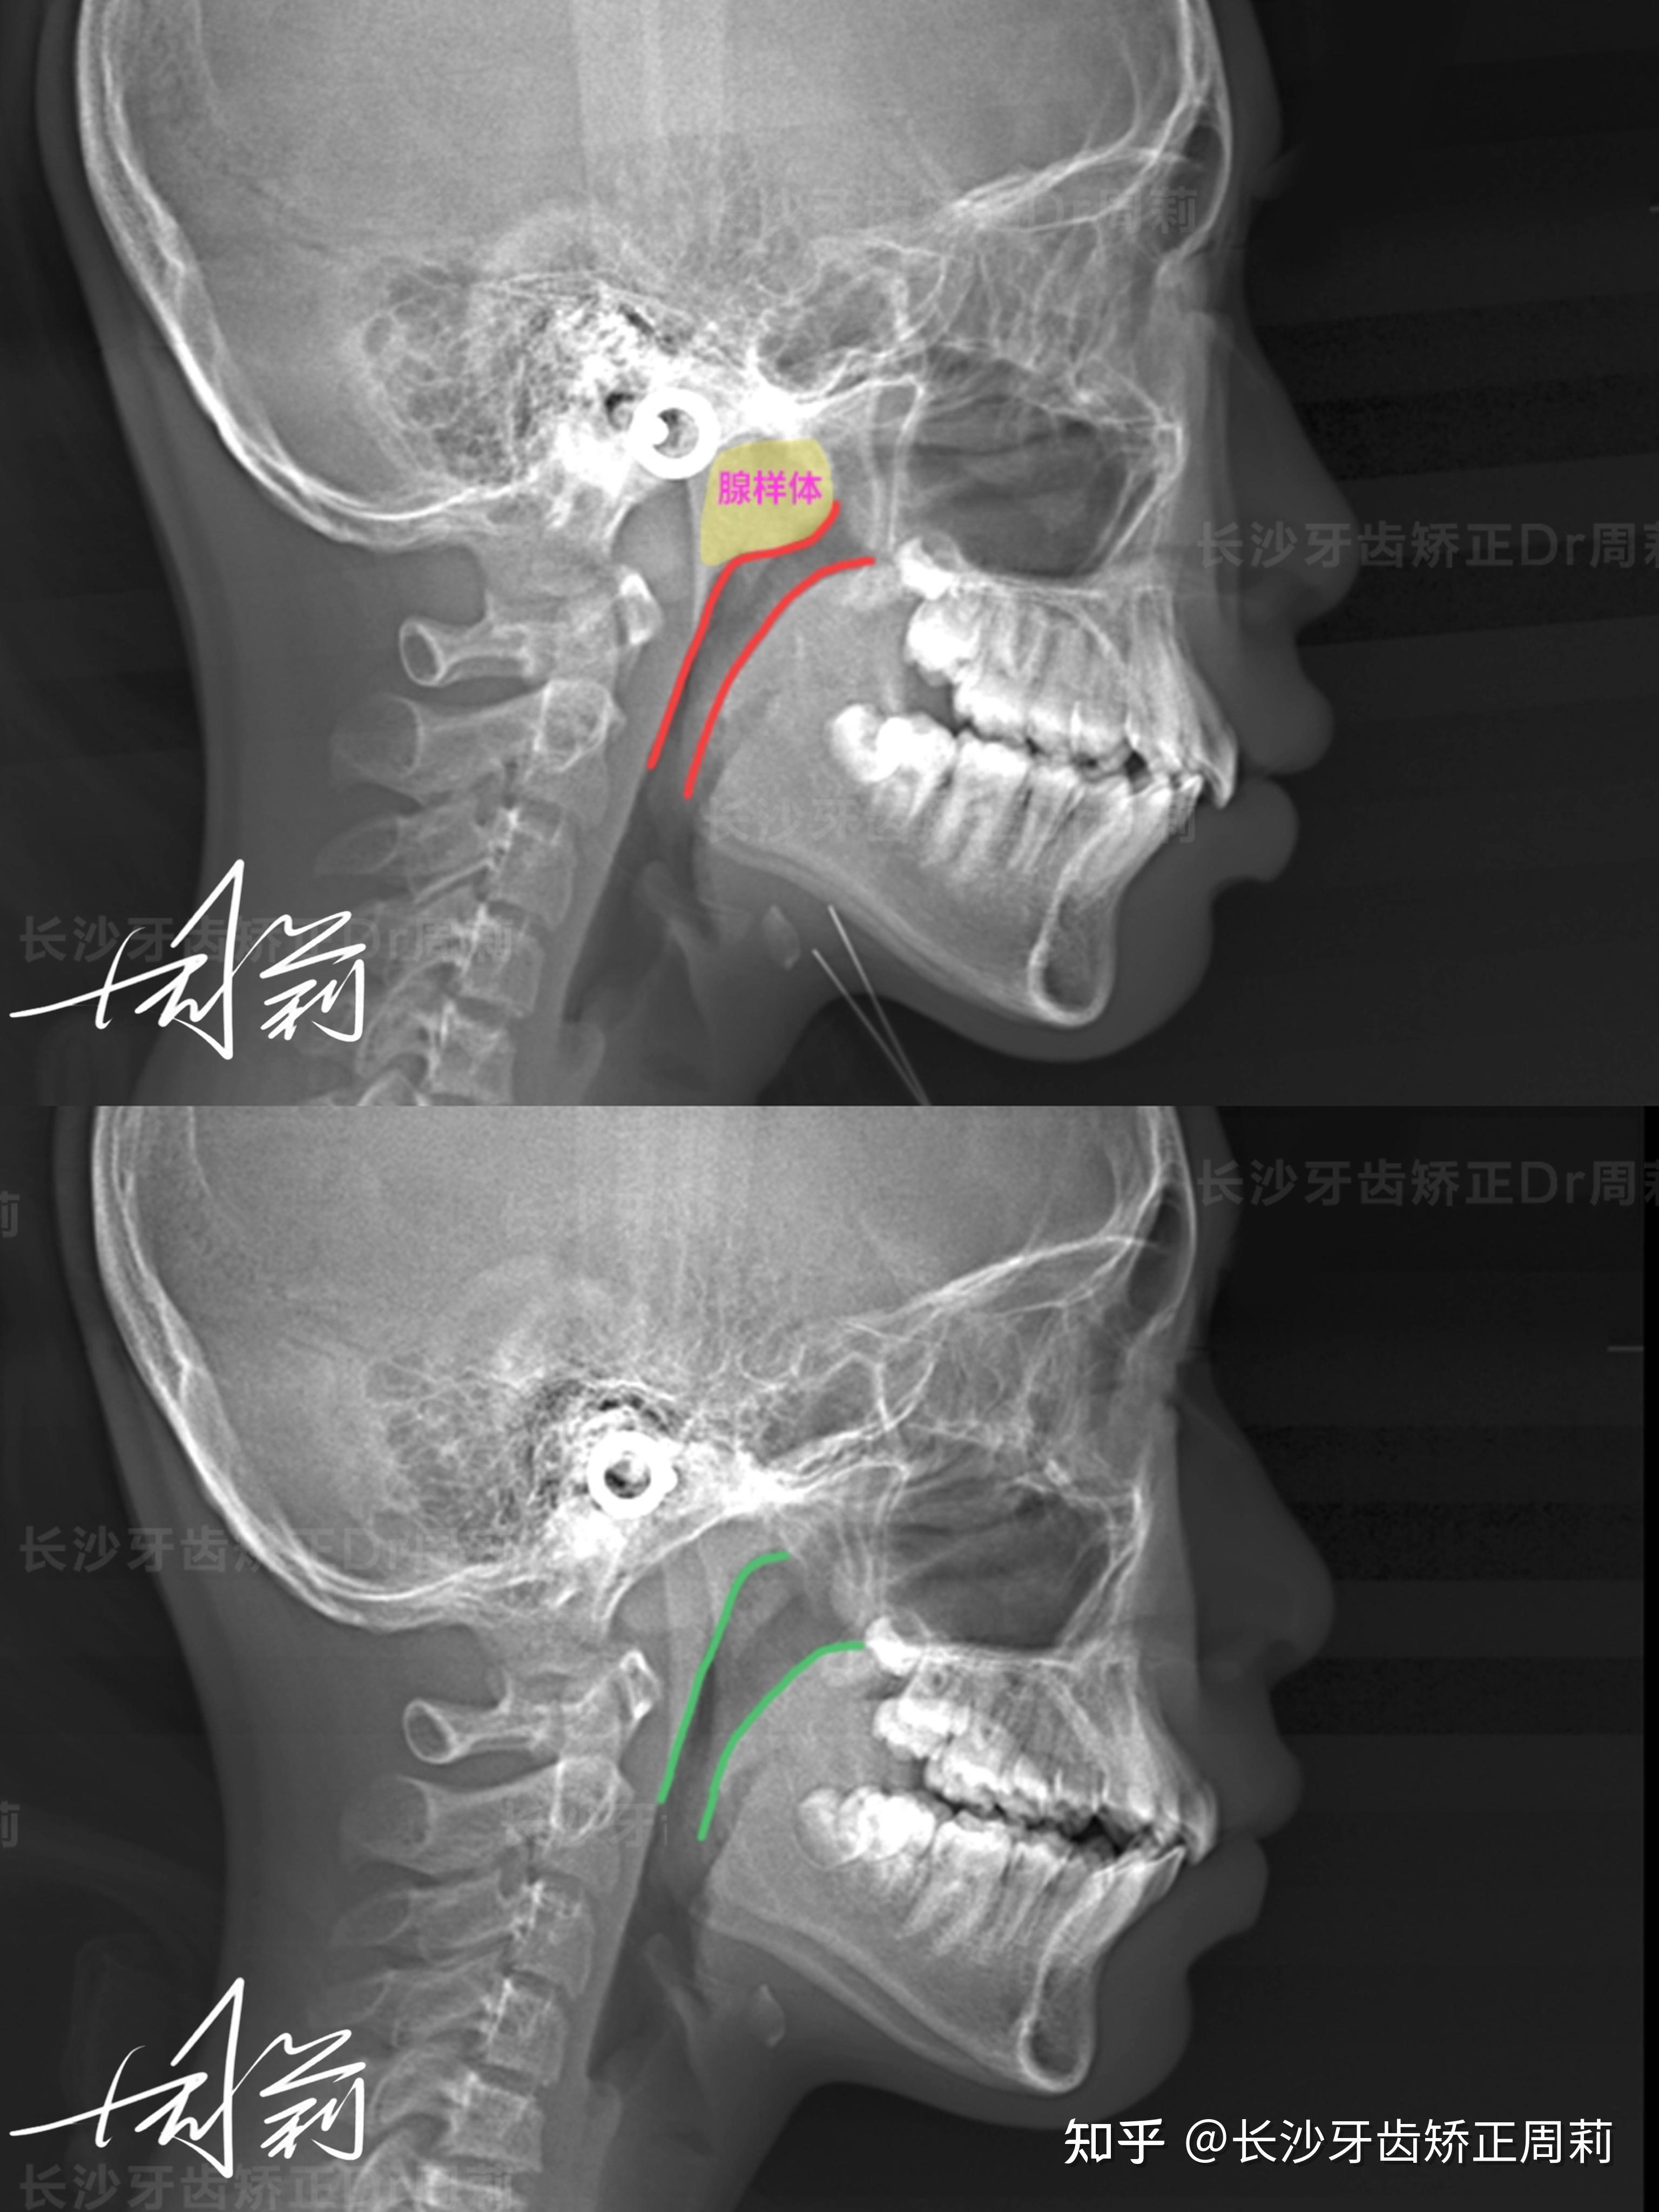

早期作品之腺样体肥大ct诊断标准 腺样体肥大 抖出健康知识宝藏

儿童腺样体肥大的ct诊断标准

腺样体肥大影像学诊断要点